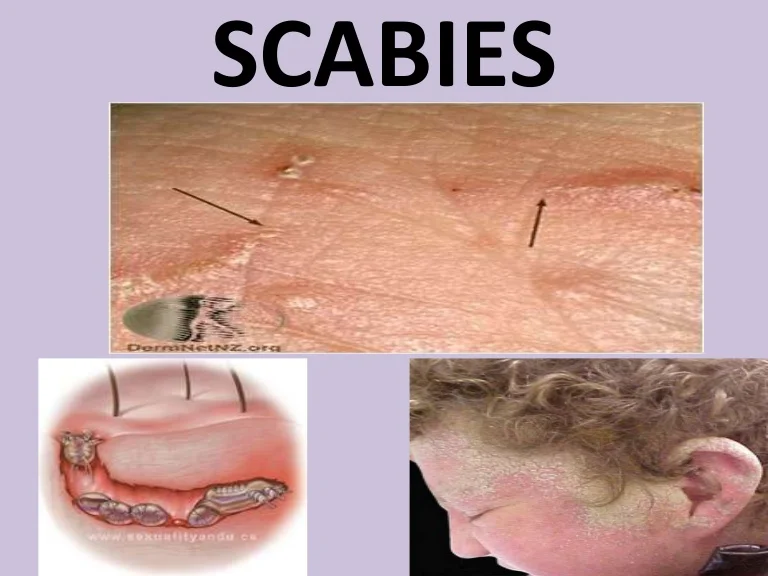

SCABİES (UYUZ)

Uyuz; Sarcoptes scabiei var. Hominis adı verilen akarın (böcek) sebep olduğu tüm dünyada yaygın olarak görülen bir hastalıktır.

Uyuz böceği deride tüneller açarak bu tünellerin içinde yaşar.

İlk defa uyuza yakalanan bir kişide belirtilerin başlaması 2-6 hafta kadar sürebilir. Ancak daha önce uyuza yakalanan bir kişide, belirtiler genellikle maruz kaldıktan 1-4 gün içinde ortaya çıkar. Hastalık belirtilerinin başlamadığı bu dönemlerde bile kişi uyuzu başkalarına bulaştırabilir.

Uyuzun en önemli belirtisi şiddetli gece kaşıntısıdır. Kaşıntı, kişinin yatağa girip ısınması ile artar ve kişiyi uykudan uyandırabilecek şiddette iken gündüzleri daha hafiftir. Kaşıntı genellikle el parmak araları, el bileğinin iç yüzü, bilekler, koltuk altları, dirsekler ve kasıklarda görülmekle birlikte tüm vücutta görülebilmektedir. Hastalığın en belirgin bulgusu parmaklar arasında dalgalı kirli bir çizgi halinde görülen, uyuz böceğinin içinde yaşadığı, gri beyaz renkli, 1-10 mm uzunluğundaki tünellerdir. Kişilerde özellikle geceleri artan şiddetli kaşıntı ve deride görülen içi su dolu keseciklerin görülmesi uyuz şüphesini arttırır.

Uyuz tedavisinin başarılı olabilmesi için uyuz hastası ile birlikte özellikle beraber yaşadığı ve uzun süreli yakın teması olan kişiler de hastalık belirtileri olup olmamasına bakılmaksızın tedavi edilmelidir. Hasta ve aynı yaşam ortamını paylaşan kişiler eş zamanlı olarak yani aynı anda tedavi olmalıdır.

Uyuz; Sarcoptes scabiei var. Hominis adı verilen akarın (böcek) sebep olduğu tüm dünyada yaygın olarak görülen bir hastalıktır.

Uyuz böceği deride tüneller açarak bu tünellerin içinde yaşar.

İlk defa uyuza yakalanan bir kişide belirtilerin başlaması 2-6 hafta kadar sürebilir. Ancak daha önce uyuza yakalanan bir kişide, belirtiler genellikle maruz kaldıktan 1-4 gün içinde ortaya çıkar. Hastalık belirtilerinin başlamadığı bu dönemlerde bile kişi uyuzu başkalarına bulaştırabilir.Uyuzun en önemli belirtisi şiddetli gece kaşıntısıdır. Kaşıntı, kişinin yatağa girip ısınması ile artar ve kişiyi uykudan uyandırabilecek şiddette iken gündüzleri daha hafiftir. Kaşıntı genellikle el parmak araları, el bileğinin iç yüzü, bilekler, koltuk altları, dirsekler ve kasıklarda görülmekle birlikte tüm vücutta görülebilmektedir. Hastalığın en belirgin bulgusu parmaklar arasında dalgalı kirli bir çizgi halinde görülen, uyuz böceğinin içinde yaşadığı, gri beyaz renkli, 1-10 mm uzunluğundaki tünellerdir. Kişilerde özellikle geceleri artan şiddetli kaşıntı ve deride görülen içi su dolu keseciklerin görülmesi uyuz şüphesini arttırır.

Uyuz tedavisinin başarılı olabilmesi için uyuz hastası ile birlikte özellikle beraber yaşadığı ve uzun süreli yakın teması olan kişiler de hastalık belirtileri olup olmamasına bakılmaksızın tedavi edilmelidir. Hasta ve aynı yaşam ortamını paylaşan kişiler eş zamanlı olarak yani aynı anda tedavi olmalıdır.